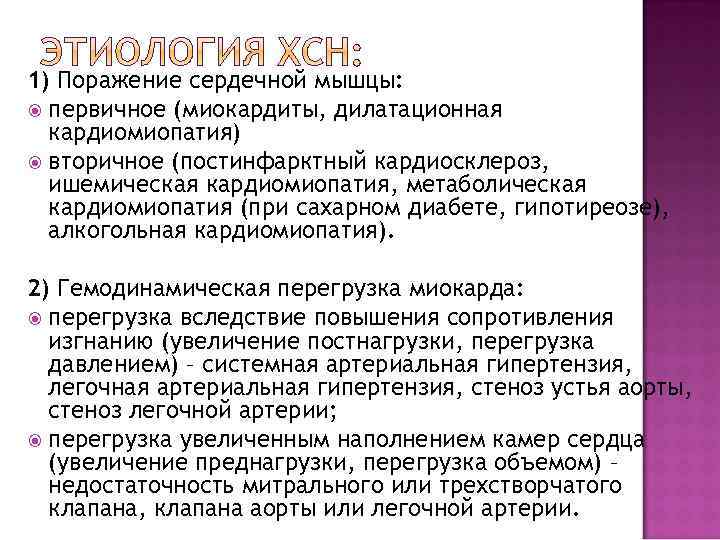

1) Поражение сердечной мышцы: первичное (миокардиты, дилатационная кардиомиопатия) вторичное (постинфарктный кардиосклероз, ишемическая кардиомиопатия, метаболическая кардиомиопатия (при сахарном диабете, гипотиреозе), алкогольная кардиомиопатия). 2) Гемодинамическая перегрузка миокарда: перегрузка вследствие повышения сопротивления изгнанию (увеличение постнагрузки, перегрузка давлением) – системная артериальная гипертензия, легочная артериальная гипертензия, стеноз устья аорты, стеноз легочной артерии; перегрузка увеличенным наполнением камер сердца (увеличение преднагрузки, перегрузка объемом) – недостаточность митрального или трехстворчатого клапана, клапана аорты или легочной артерии.

1) Поражение сердечной мышцы: первичное (миокардиты, дилатационная кардиомиопатия) вторичное (постинфарктный кардиосклероз, ишемическая кардиомиопатия, метаболическая кардиомиопатия (при сахарном диабете, гипотиреозе), алкогольная кардиомиопатия). 2) Гемодинамическая перегрузка миокарда: перегрузка вследствие повышения сопротивления изгнанию (увеличение постнагрузки, перегрузка давлением) – системная артериальная гипертензия, легочная артериальная гипертензия, стеноз устья аорты, стеноз легочной артерии; перегрузка увеличенным наполнением камер сердца (увеличение преднагрузки, перегрузка объемом) – недостаточность митрального или трехстворчатого клапана, клапана аорты или легочной артерии.

3) Нарушение диастолического наполнения желудочков (стеноз левого или правого атриовентрикулярного отверстия, экссудативный и констриктивный перикардит, гипертрофическая и рестриктивная кардиомиопатия). 4) Повышение метаболических потребностей тканей (ХСН с высоким минутным объемом) В настоящее время главными причинами ХСН остаются ишемическая болезнь сердца (ИБС) и артериальная гипертензия.

3) Нарушение диастолического наполнения желудочков (стеноз левого или правого атриовентрикулярного отверстия, экссудативный и констриктивный перикардит, гипертрофическая и рестриктивная кардиомиопатия). 4) Повышение метаболических потребностей тканей (ХСН с высоким минутным объемом) В настоящее время главными причинами ХСН остаются ишемическая болезнь сердца (ИБС) и артериальная гипертензия.